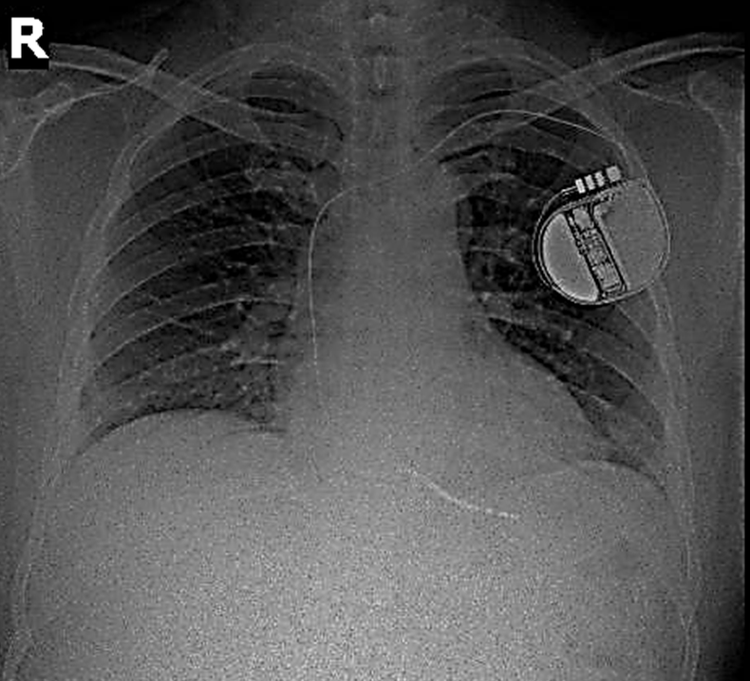

Hình ảnh máy phá rung tim trên phim chụp Xquang. Ảnh BV

Sau đó người bệnh đã được cấy máy khử rung tim (ICD) – một thiết bị nhỏ đặt trong lồng ngực, có nhiệm vụ phát hiện và ngăn chặn kịp thời các cơn rối loạn nhịp tim nguy hiểm bằng xung điện.

Phẫu thuật cấy máy phá rung tim tự động là một trong những kỹ thuật cao, yêu cầu bác sĩ thực hiện phải là người có chuyên môn sâu, giàu kinh nghiệm về tạo nhịp tim. Máy phá rung tim được cấy ghép gồm một dây điện cực kết nối từ máy vào buồng tim phải qua đường tĩnh mạch dưới đòn. Máy sẽ ghi nhận và theo dõi tất cả mọi hoạt động điện học của tim.

Khi tim xuất hiện tình trạng rối loạn nhịp nguy hiểm, tín hiệu bất thường này sẽ chuyển tới máy phá rung, máy sẽ gửi 1 cú sốc điện mạnh để cắt những cơn rối loạn nhịp, đưa trái tim trở về nhịp co bóp bình thường, ngăn ngừa đột tử.